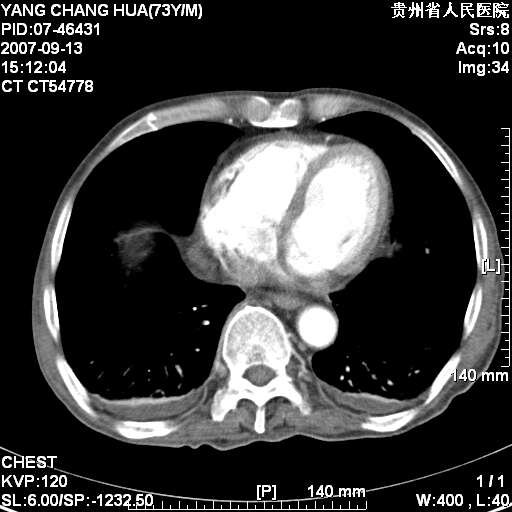

标题: CT9726:M73Y,患者因吞咽困难及腹痛半月入院!全身浅表淋巴结 [打印本页]

标题: CT9726:M73Y,患者因吞咽困难及腹痛半月入院!全身浅表淋巴结

图像没有传全。肺部为感染性病灶;肺囊肿;双侧胸腔积液;肝脾肿大;腹水。

临床诊断 恶性淋巴瘤! !

双肺部为感染性病灶.双侧胸腔积液;肝脾肿大;腹水.

双肺部为感染性病灶.双侧胸腔积液;肝脾肿大;脾脏密度不均,不除外脾侵润?腹水.

恶性淋巴瘤,双肺部也是.

双肺部为感染性病灶.双侧胸腔积液;肝脾肿大;腹水

考虑.恶性淋巴瘤

图片不全.就这几张图片.无法诊断淋巴瘤的,我考虑:双肺部为炎性病灶.双侧胸腔积液;肝脾肿大;腹水

双肺点片状影,以双上肺改变明显.双侧胸腔积液.为感染性病灶,但不除外结核.

肝脾都大..

我们主任诊断结核 !

双上肺继发型肺结核。

双侧胸腔积液。

肺大泡。

食管癌未除。

肝脾肿大。

少量腹水。

双肺散在斑片状及多发小结节状阴影,边缘模糊,双上肺野明显,双侧胸膜腔少量积液,纵隔及肺门区未见明显肿大淋巴结,肝脾肿大,脾内见多发低密度区,结合临床考虑恶性淋巴瘤(肺内表现为肺炎肺泡型),单看影像表现,肺结核不能排除。建议结合实验室检查或表浅淋巴结活检。

肺部为;恶性淋巴瘤;双侧胸腔积液;肝脾肿大;腹水。